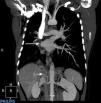

Chest radiograph showed a resolving consolidation together with decreased right lung volume with a mediastinal shift to that side. The computed tomography (CT) scan is shown in Fig. 1. Bronchoscopy was performed, with the following findings: absence of right upper lobe bronchus; in its place was the opening of 2 accessory bronchi that prevented the bronchoscope from advancing. The opening of the apical and paracardiac bronchus of the right lower lobe could not be seen either. Spirometry revealed a moderately restrictive pattern, while the echocardiogram showed mild aortic stenosis with no pulmonary hypertension findings.

Finally, an angiography was performed. This confirmed all the findings described in the CT and also showed that part of the collateral system formed to supply the right lung came from an inferior phrenic artery (Fig. 1).